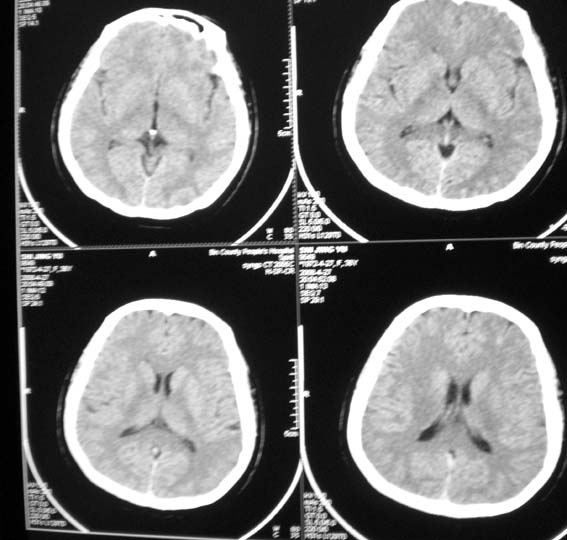

标题: CT13124:女,36岁,常短暂性意识丧失。

女,36岁,常短暂性意识丧失。

右顶部放射冠部白质内异常灰质团块影 考虑灰质移位症可能

患者短暂性意识丧失考虑为癫痫小发作

另外要注意患者ecg或holter检查,以除外心源性晕厥可能

鞍上池右侧旁脑质内见团块稍高密度影,建议mr检查。